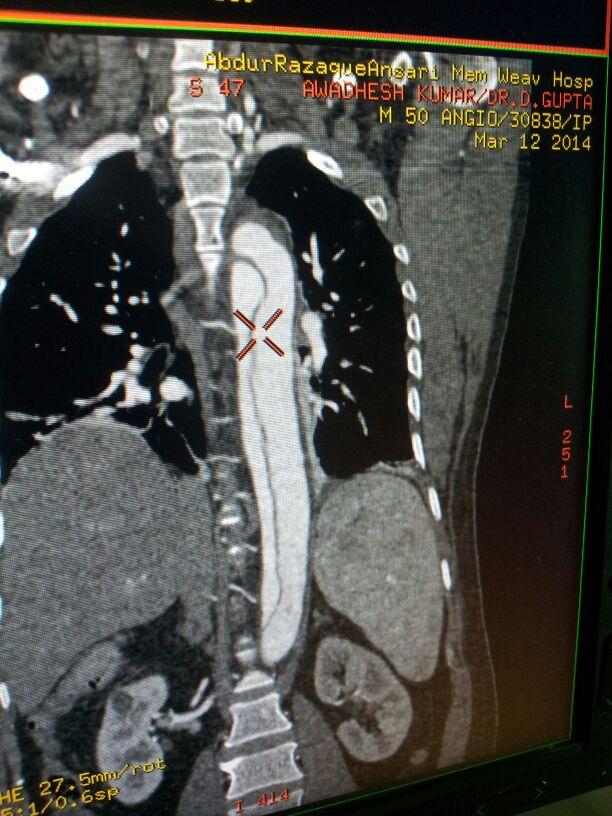

EVAR